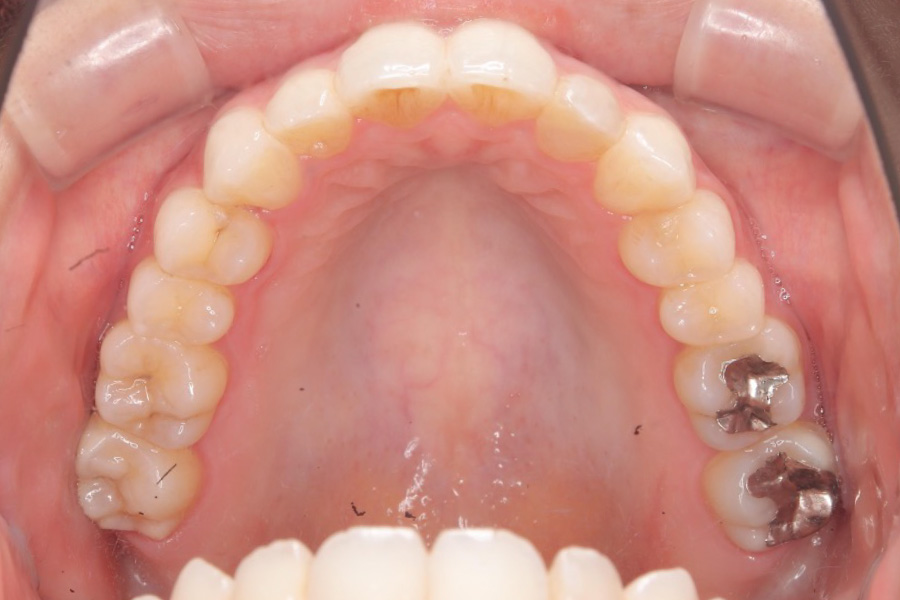

【30代女性】八重歯を

インビザライン矯正で治療したケース

治療後

主訴 八重歯

期間 2年半

費用 220,000円〜660,000円

(デンタルローン 3,100〜6,600円/月)

治療内容 インビザライン矯正

非抜歯